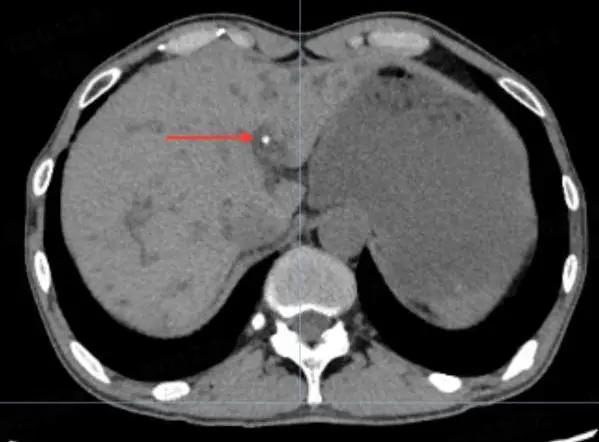

全腹CT提示:

胆囊内团簇高密度影

胆总管下段与肝内也存在高密度影

疑似胆总管结石,胆囊结石

(腹部CT“肝吸虫”,疑似“虫卵或死虫”)